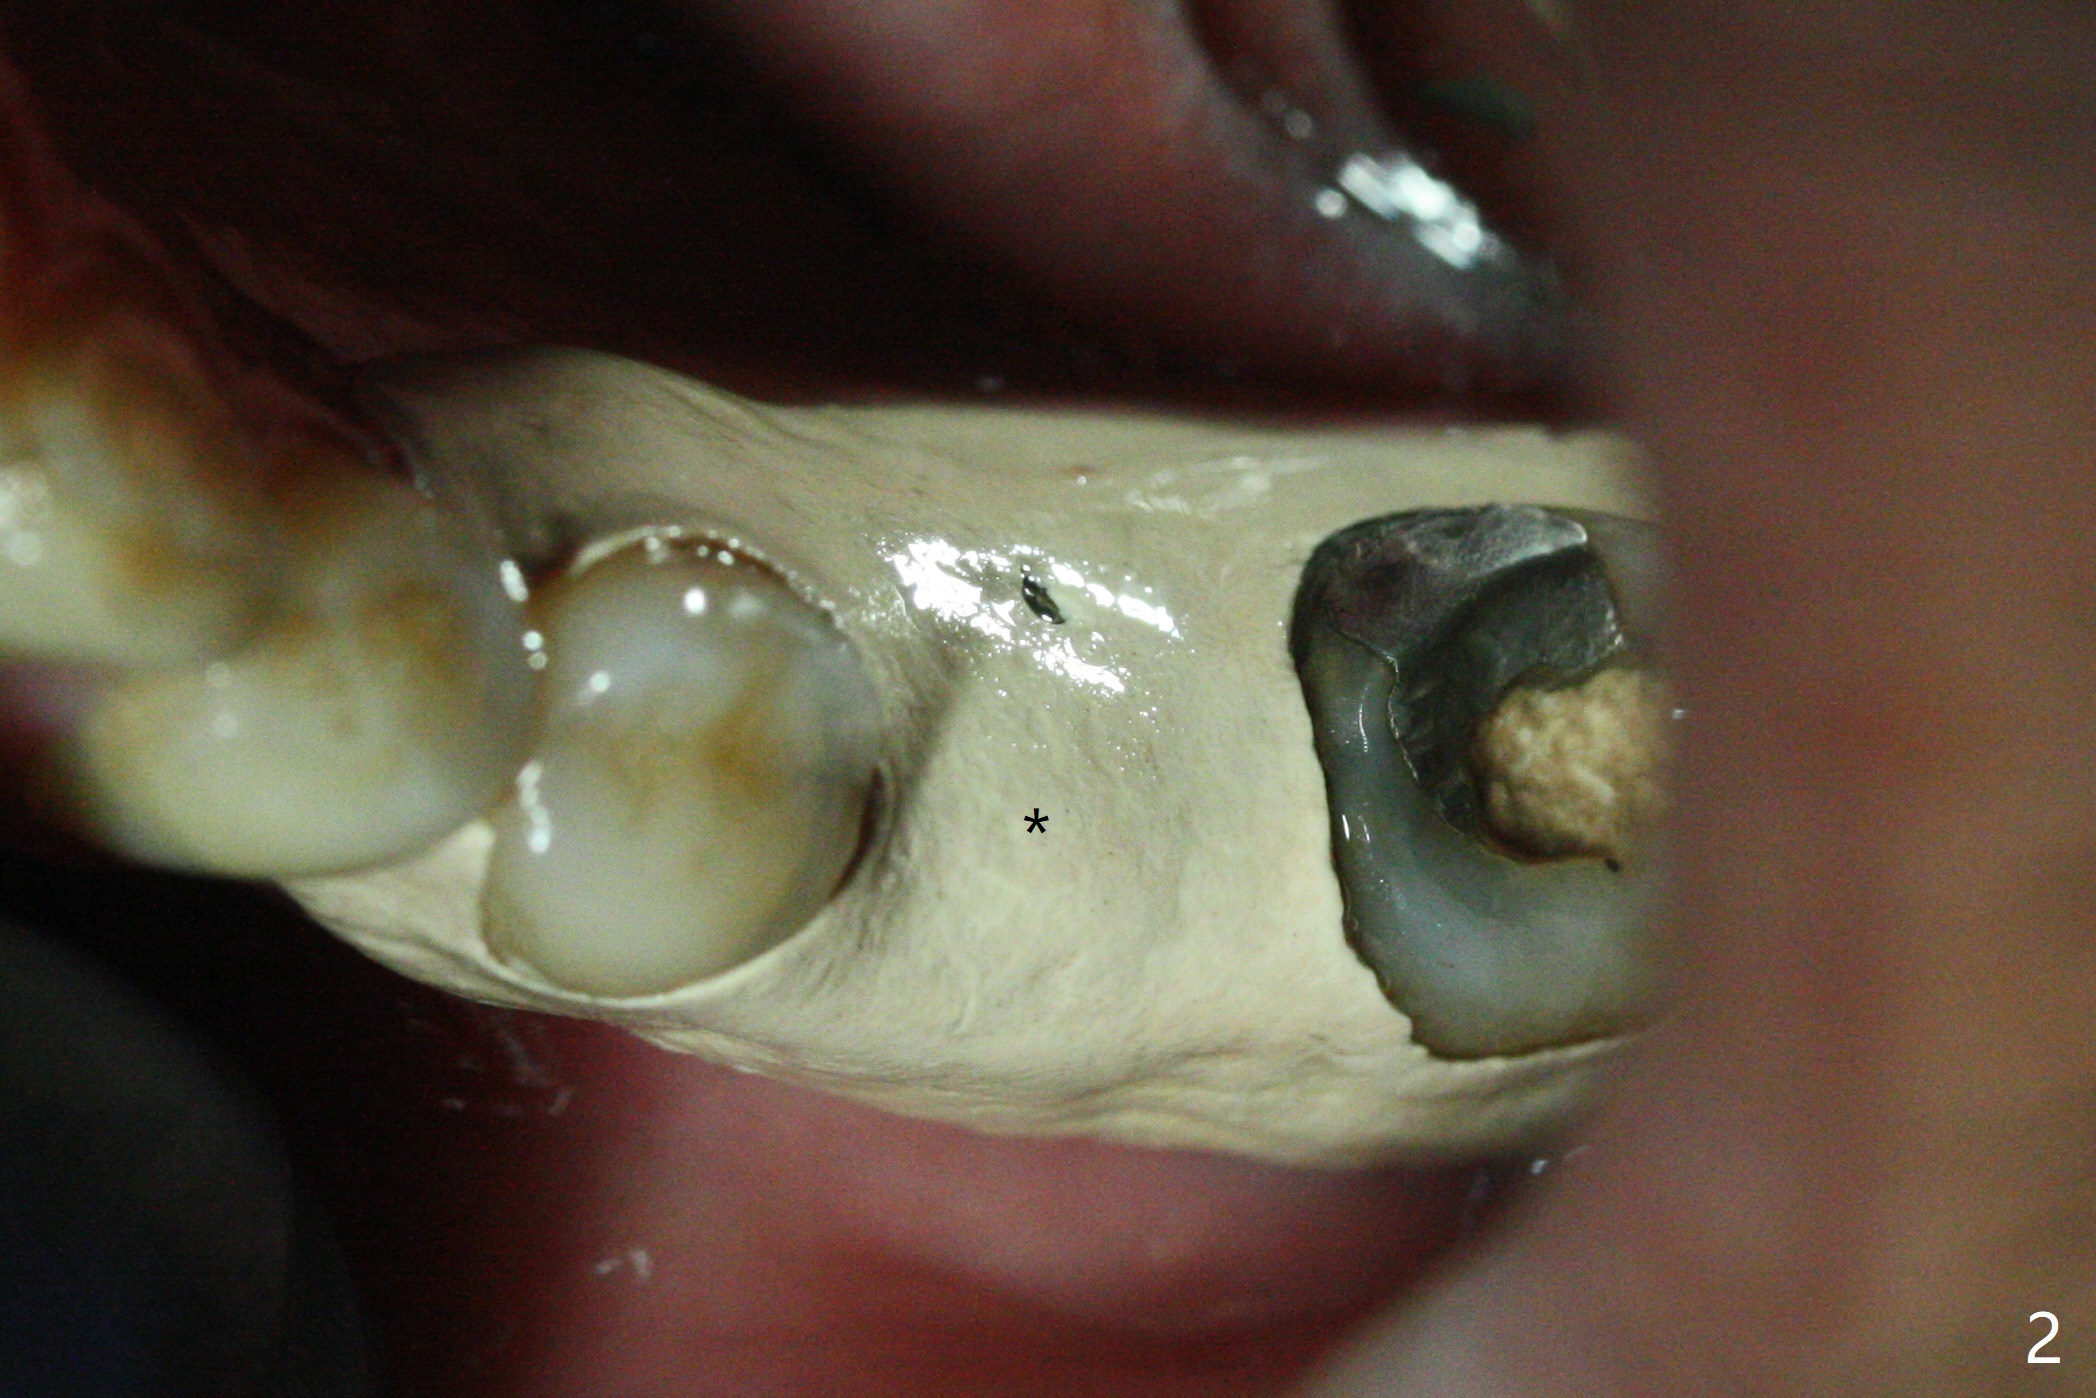

Due to low bone density associated with no bone graft after extraction and possible accessory nerve, osteotomy at #19 is underprep in diameter (3.5 vs. 4.0x8.5 mm), but overprep finally in length (3.5x10 mm) with 1 ampule of Lidocaine. Insertion torque associated with 4.0 and 4.5 mm cortical taps and 4.5x10 mm implant (Fig.1) is between 30-55 Ncm. Since the implant is covered by buccal and lingual bone associated with deep placement, no bone graft is conducted. The lingual gingiva has minor laceration near the access. Periodontal dressing is applied. It remains in place a week postop due to retention associated with the healing abutment (Fig.2 *). A long abutment is placed for restoration 4 months postop (Fig.3), increasing the chance of abutment screw loosening (as compared to immediate implant) if the abutment is incompletely seated.